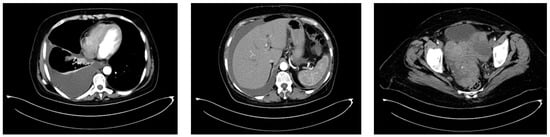

2.2.3. Examinations and Investigations